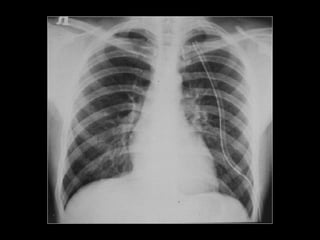

NSTEMI - ACS 56Jahre, weiblich Seit 3 Tagen Herzschmerzen, zuletzt auch in Ruhe Cholesterin Familiäre Belastung Übergewicht Troponin T hs 67 pg/ml [0 -14] EKG Kardinal Schwarzenberg´sches Krankenhaus, Innere Medizin, Freitag 29. Juni 2012

EKG - Extremitätenableitungen Kardinal Schwarzenberg´sches Krankenhaus, Innere Medizin, Freitag 29. Juni 2012